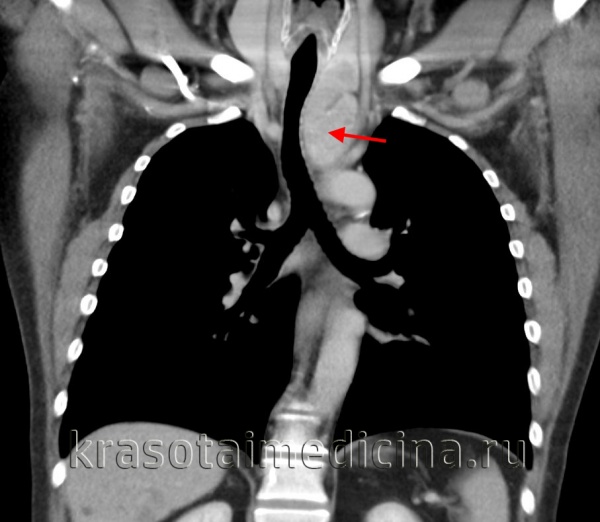

(а) У мужчины 27 лет при КТ с контрастным усилением в левой паравертебральной области определяется параганглиома, интенсивно накапливающая контрастное вещество. Параганглиомы являются гиперваскулярными опухолями, вблизи которых часто выявляются расширенные сосуды. Вследствие этого для планирования хирургического вмешательства или эмболизации может выполняться ангиография.

(б) У этого же пациента при МРТ на Т2ВИ визуализируется гиперинтенсивная зона в структуре объемного образования, что характерно для параганглиомы.

(а) У пациента с параганглиомой в средостении при КТ с контрастным усилением в области бифуркации трахеи определяется объемное образование, сдавливающее правую легочную артерию и накапливающее контрастное вещество. В грудной клетке параганглиомы чаще всего формируются вдоль симпатического ствола, блуждающего нерва или в сердце.

(б) У этого же пациента при МРА в кососагиттальной проекции визуализируется объемное образование, контрастирующееся немного гетерогенно. Интенсивное контрастирование при введении гадолиния является характерным признаком параганглиомы.